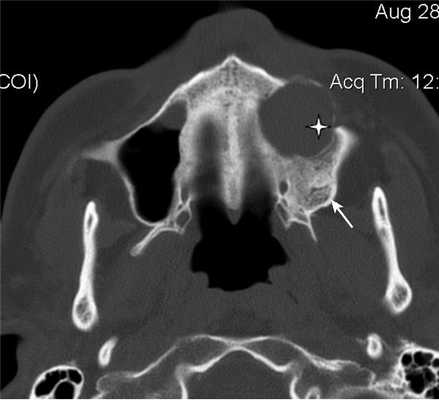

Пломбировочный материал был обнаружен у 38 (22,8%) пациентов (рис. 2). Из них у 34 (20,4%) больных в подслизистом слое нижней стенки синуса, у 4 (2,4%) — в верхнем отделе у медиальной стенки синуса (рис. 3). У 8 (4,8%) пациентов диагностированы ошибки стоматологической имплантации: верхушка импланта была погружена в полость синуса, что стало причиной развития хронического одонтогенного верхнечелюстного синусита, а также осложнений в виде хронического полисинусита (n=4; 2,4%).

Рис. 3. КЛКТ. Сагиттальная реконструкция, правый верхнечелюстной синус. Пациент У., 48 лет. Диагноз: правосторонний одонтогенный хронический верхнечелюстной синусит. Зубы 1.6 и 1.7 после эндодонтического лечения, отмечается выведение пломбировочного материала за верхушки корней зуба 1.6 (материал располагается в костной ткани альвеолярного отростка и в подслизистом слое синуса). Определяется разрежение костной ткани в области корней 1.6 и 1.7, костная стенка синуса в данной области не прослеживается (стрелка). В нижнем отделе синуса определяется утолщение слизистой оболочки до 10 мм, в верхнемедиальном отделе синуса визуализируется инородное тело неправильной формы металлической плотности (соответствует фрагментам пломбировочного материала).

Больной Л., 44 года, 15 лет назад терапевтическое лечение 16-го зуба с последующей перепломбировкой; 5 лет назад было осуществлено удаление 16-го зуба. В настоящее время больной обратился за помощью в ЛОР-отделение по поводу давящих болей в верхнечелюстной области справа. Больному была выполнена РКТ верхнечелюстных пазух (рис. 5, а, б), которая показала, что правая пазуха тотально заполнена мягкотканным содержимым и высокоплотным пломбировочным материалом. Отмечается утолщение костных стенок правой верхнечелюстной пазухи и прилежащей ретромаксиллярной клетчатки (–52 HU справа, –86 HU слева)

Рис. 5. Рентгеновская компьютерная томограмма верхнечелюстных пазух. Аксиальная проекция: костное окно (а), мягкотканное окно (б).